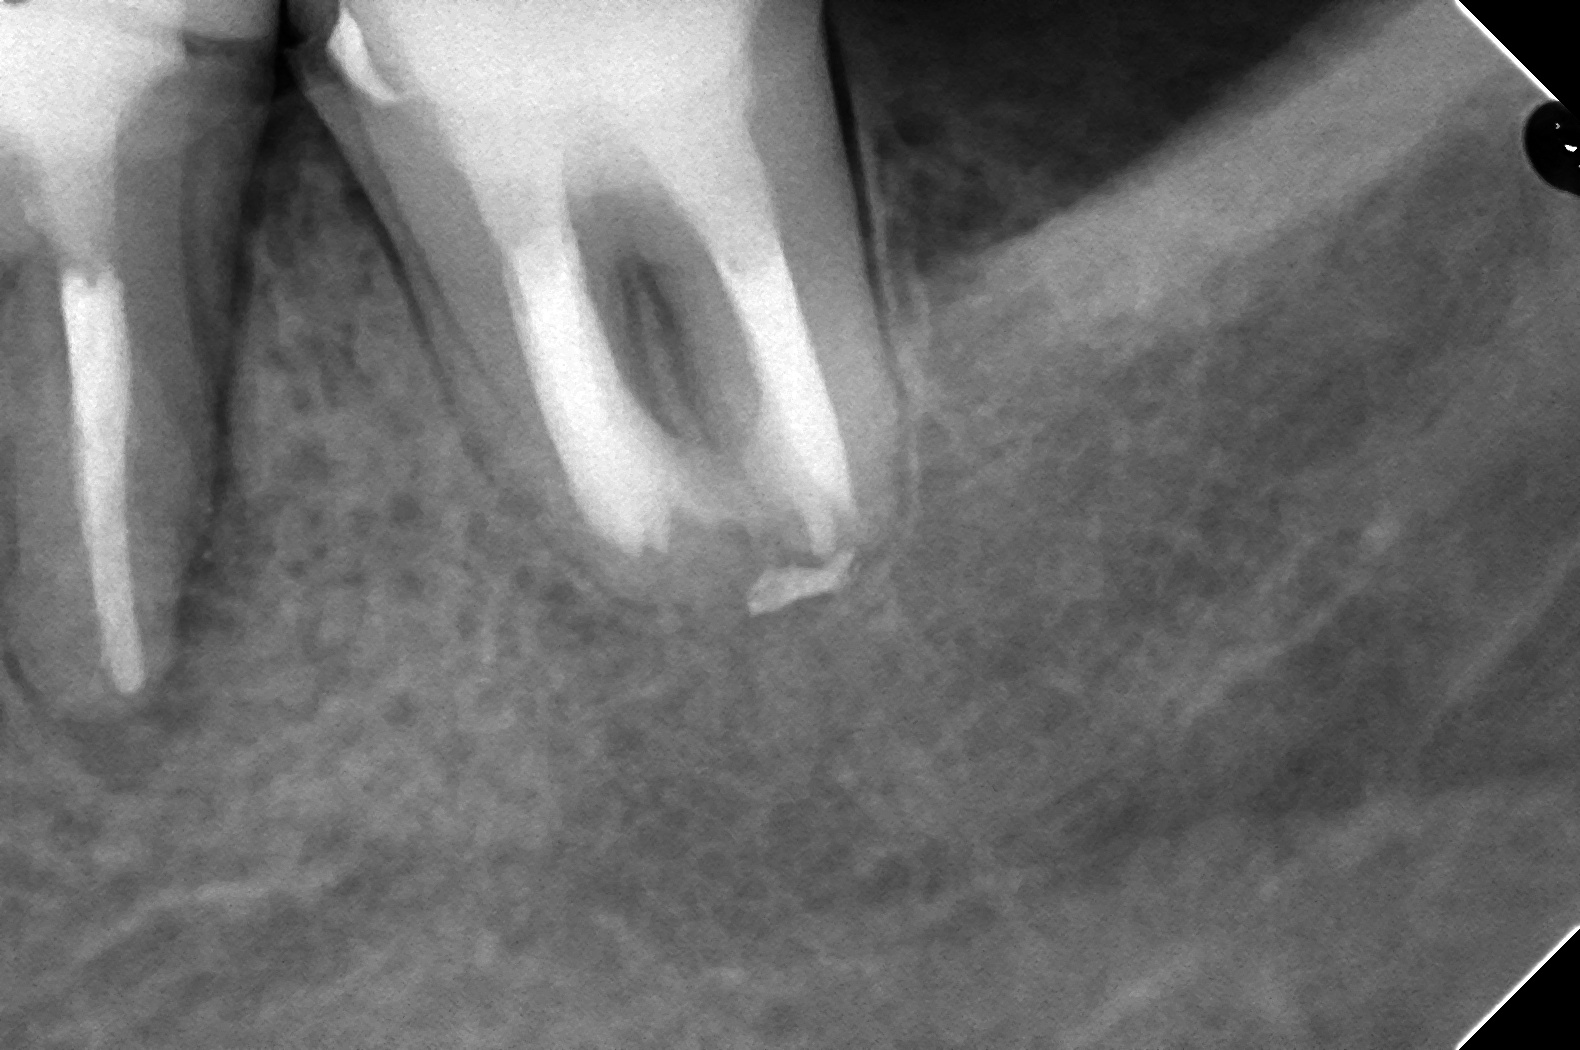

DB121236_151208182043(調整後)紹介元の先生から37番の依頼を頂いたのだが、36番に瘻孔があったためGPを挿入している

原因かどうかはわからないんですが

DB121236_151208182043(調整後)

太めに形成しているのにも関わらず、GPの取り残しが・・・

これは、M根とD根が細い隙間(イスムス)に入っちゃってるからなんですね。